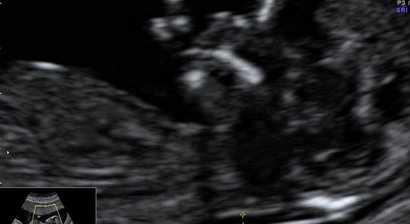

2D, 3D, 4D Ultraschall

Die Ultraschalluntersuchung ist heute von einer kompetenten Frauenarzt-Praxis nicht mehr wegzudenken. Wir verfügen seit 2015 über ein extrem hochwertiges Ultraschallgerät, das neben einer sehr guten Bildauflösung Techniken wie 3D Ultraschall, 4D Ultraschall und verbesserten Doppl...